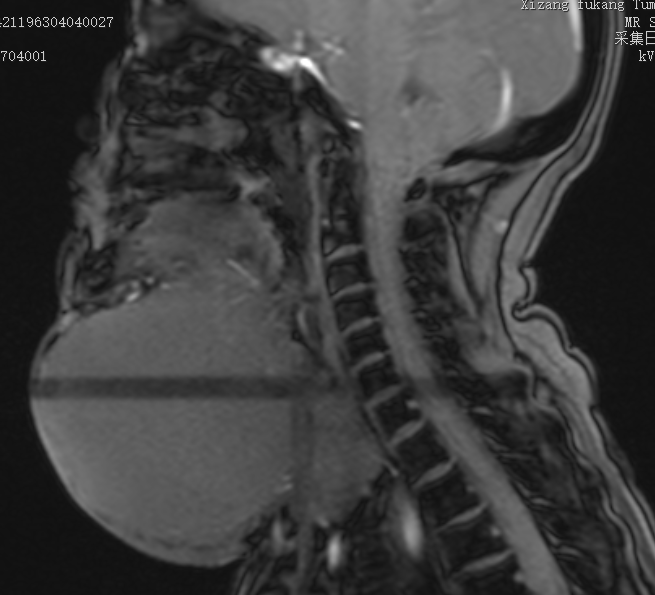

图片▲患者颈部CT影像

患者为60岁女性,主因“发现颈部肿物40余年”入院,自述患者40年前无意间发现颈部肿物,约蚕豆样大小,无红肿疼痛不适,无吞咽困难及声音嘶哑不适,无畏寒发热,无午后低热盗汗,未予重视。后颈部肿物逐渐增大,约1.5拳头样大小,伴坠胀疼痛不适,呈阵发性刺痛,活动时疼痛症状加重,托起肿物时疼痛较前好转,无呼吸困难及进食障碍。既往无特殊病史。颈软,无抵抗,颈部皮肤无红肿,右侧颈部可见约14*10*13cm巨大不规则肿块边界较清楚,质地稍硬,活动度尚可,肿物予周围组织稍粘连,轻压痛,周围皮肤温度不高,肿物未触及波动感。患者本人非常着急求医,却被多家医院拒绝收治,建议去内地治疗,由于患者家庭经济困难,通过朋友介绍找到陈新主任。经主任检查患者后,认为西藏阜康肿瘤医院有能力、有责任为患者解除病痛,决定收治该患者。